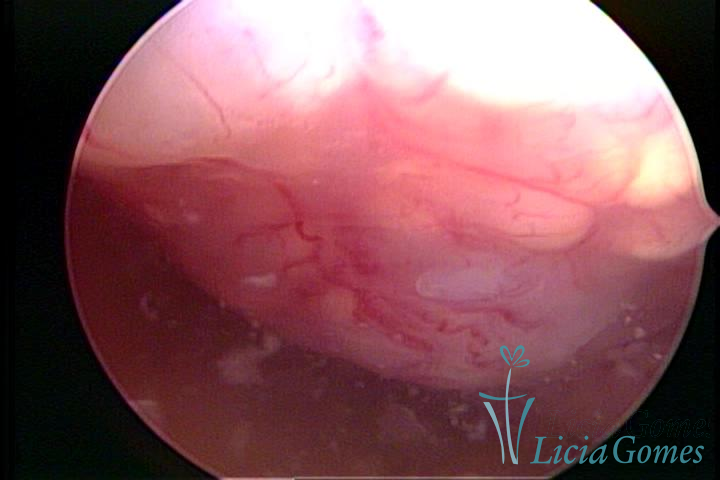

Este pode apresentar uma gama variável de aspectos macroscópicos, com aspecto pseudopolipoide; lembrando tecido cerebroide ou com reação deciduoide;a vascularização superficial é mais evidente e com vasos em formatos de saca-rolha ou espirais visualizando também a vascularização com atípias, com aumento do calibre dos vasos superficiais, pode ser encontrado também tecido em necrose, poderá haver um pequenos dendritos (papilomatoso).